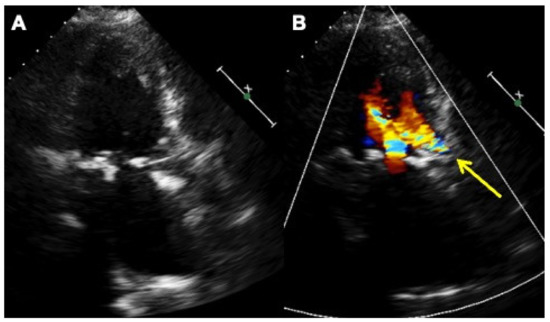

A Comparison of the Catheter-Based Transapical and Surgical Treatment Modalities for Mitral Paravalvular Leak

Background: There is a lack of studies where the outcomes of mitral paravalvular leak treatment were compared between surgery and catheter-based closure. The aim of this study was to compare the outcomes of re-do surgery with transapical catheter-based paravalvular leak closure. Methods: This [...] Read more.

Background: There is a lack of studies where the outcomes of mitral paravalvular leak treatment were compared between surgery and catheter-based closure. The aim of this study was to compare the outcomes of re-do surgery with transapical catheter-based paravalvular leak closure. Methods: This is a retrospective observational study at a single institution; 76 patients were included. According to the treatment, two groups were formed: the “Surgical” group (49 patients after re-do surgery) and the “Catheter” group (27 patients after transapical catheter–based treatment). Results: In-hospital myocardial infarction occurred in 9 (18%) cases in the “Surgical” group and none in the “Catheter” group, p = 0.018. Procedure-related life-threatening bleeding occurred in 9 (18%) patients in the “Surgical” group and none in the “Catheter” group, p = 0.018. Nine (18%) patients died in 30 days in the “Surgical” group, and none died in the “Catheter” group, p = 0.039. A mean follow-up was 3.3 years. No difference was found between the groups by the degree of residual paravalvular regurgitation either at discharge or at follow-up. During the follow-up, 19 (39%) patients died in the “Surgical” group and 2 (7%) among the “Catheter” patients. Conclusions: Transapical catheter-based closure of mitral paravalvular leak seems to be a safer treatment procedure than conventional re-do surgery, and the effectiveness of these procedures does not differ. Full article

Show Figures

Figure 1